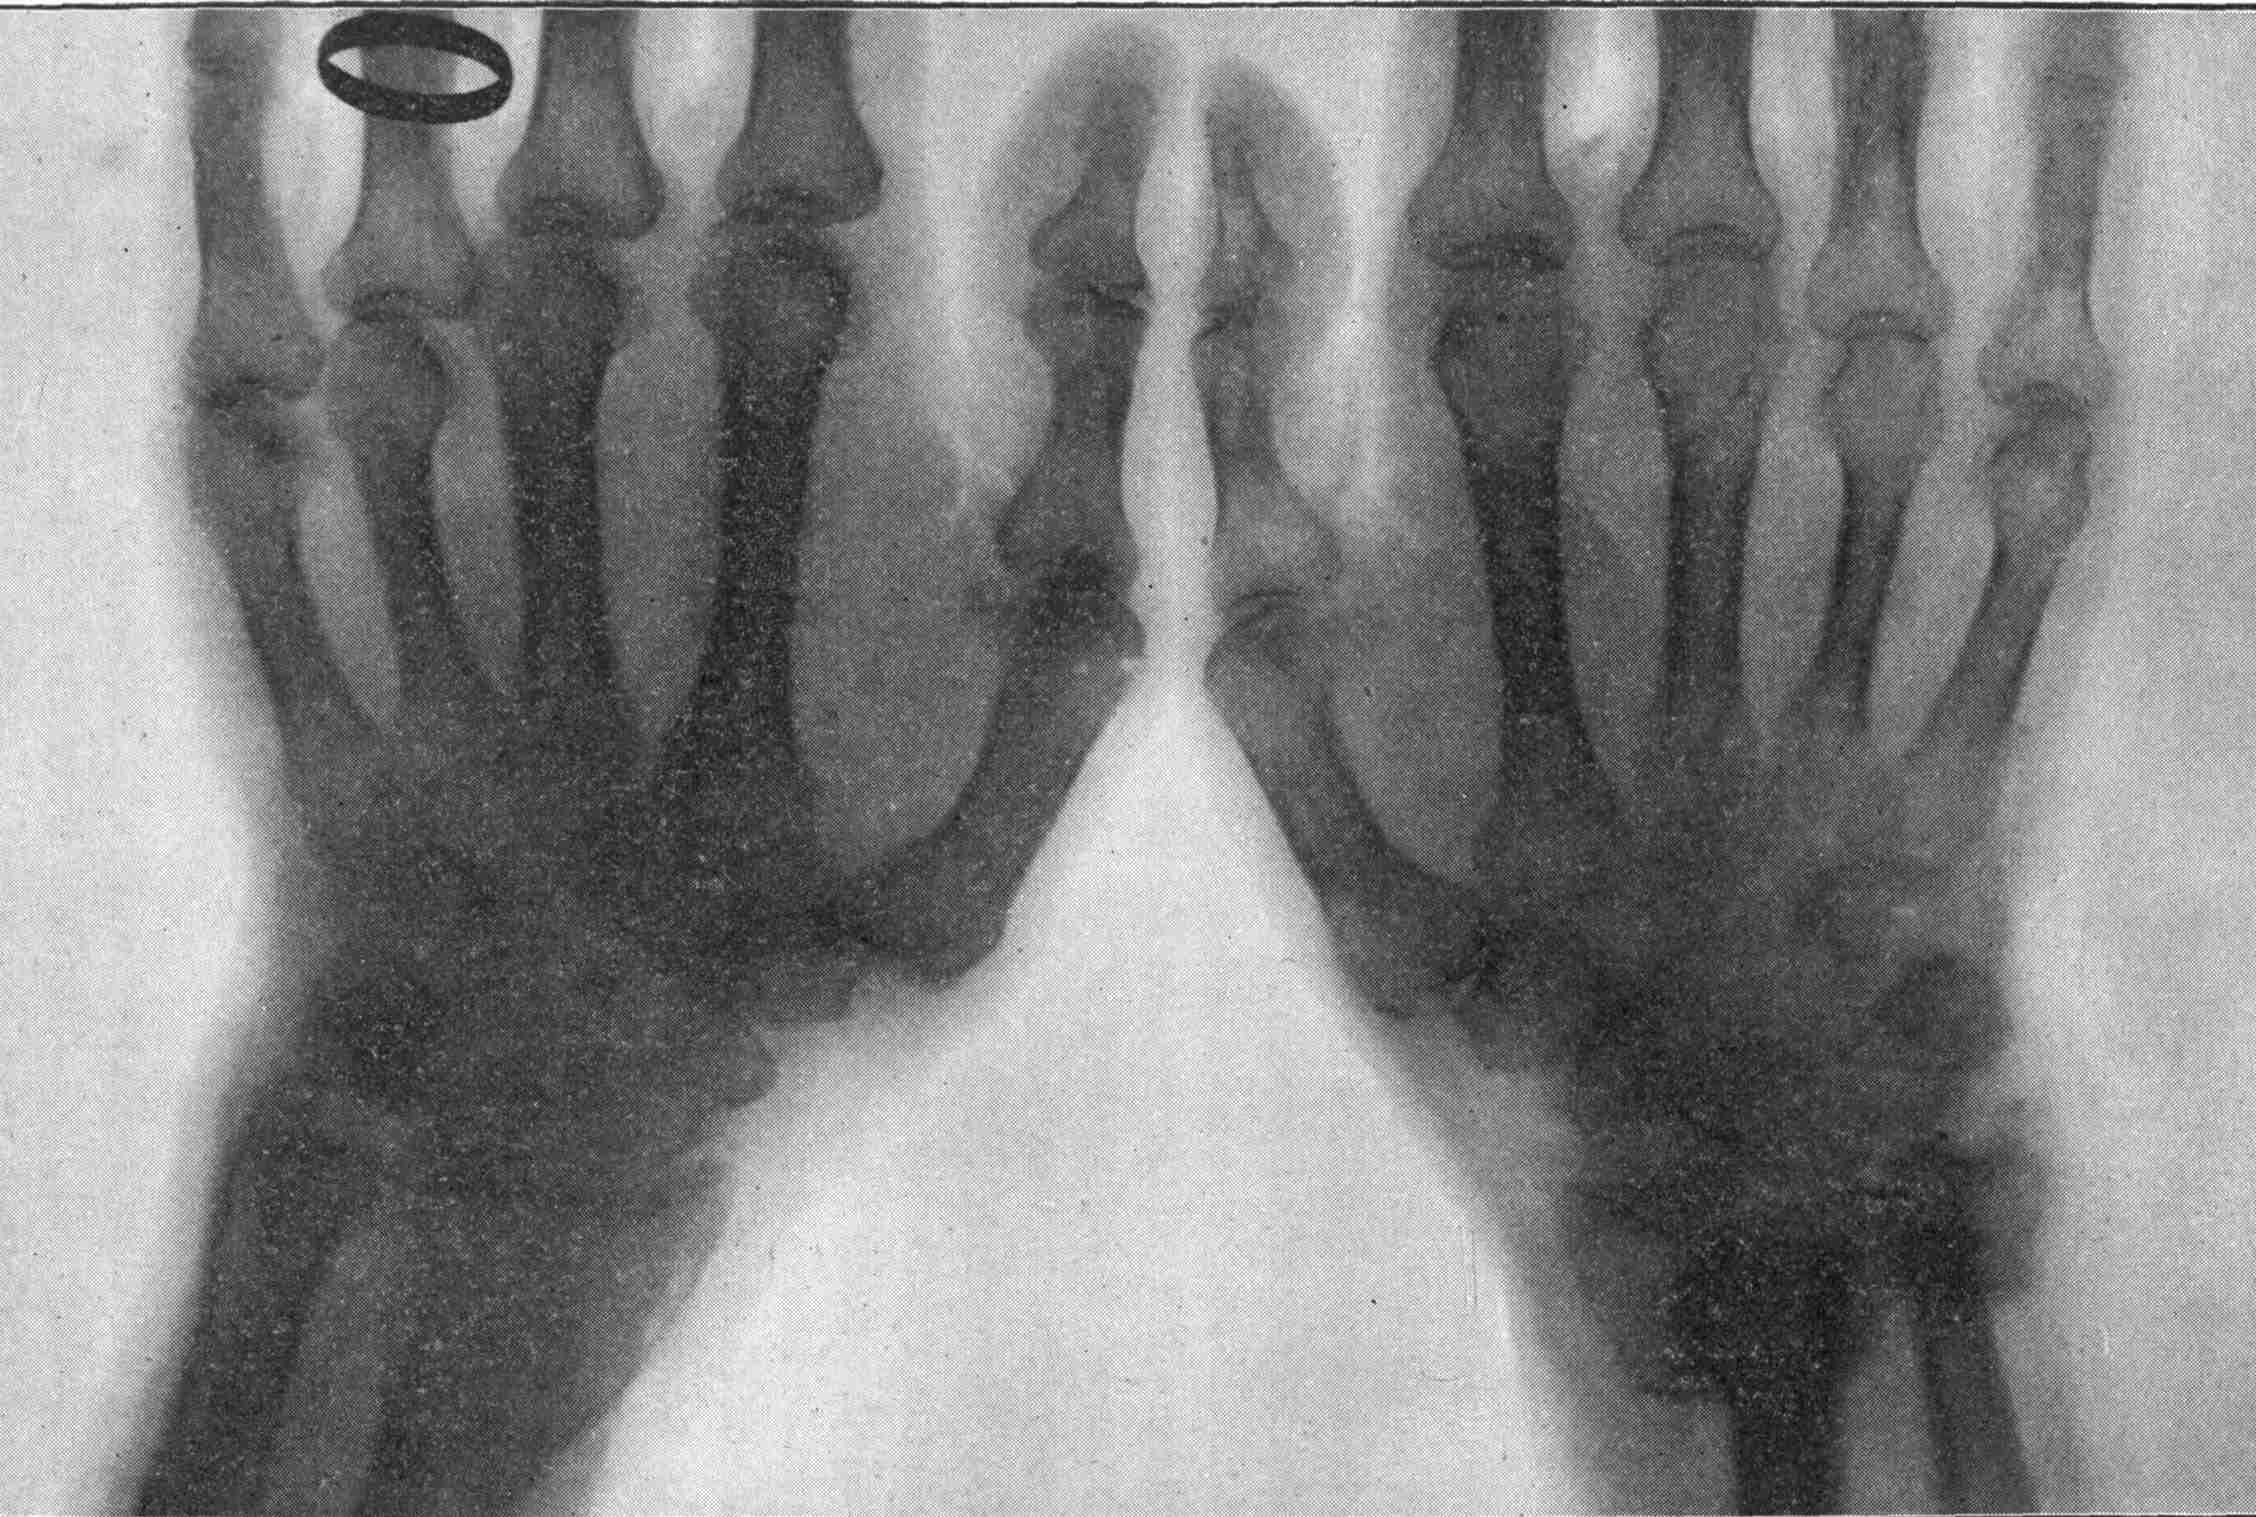

Fig. 3.—Ribs.